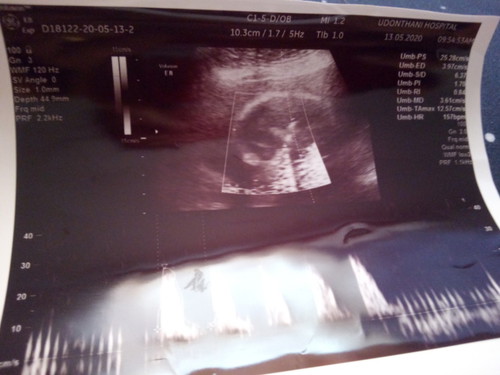

21 w. แล้วค่ะ ยังไม่ทราบเพศลูกเลย ใครพอจะดูออกช่วยแนะนำทีค่ะ